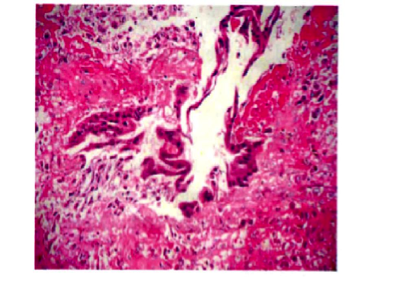

Bệnh nhân Đỗ Thị Hải Y. 38 tuổi, PARA 2002, sống tại Ninh Bình; tiền sử nội ngoại khoa bình thường; hành kinh đúng ngày dự kiến, nhưng số lượng ít. Ngày 05/08/2008, bệnh nhân đau bụng đột ngột, không nôn, không sốt, có dấu hiệu choáng. Bệnh viện Ninh Bình nghi TNTC vỡ, chuyển đến Bệnh viện Phụ Sản Trung ương trong tình trạng không choáng, mạch 80/phút, huyết áp 100/70mmHg, nhịp thở 19 lần/phút. Bụng có phản ứng. Âm đạo có máu đỏ thẫm, cổ tử cung đóng kín, tử cung to hơn bình thường, di động dễ, phần phụ không có khối, cùng đồ sau đầy, ấn đau, chọc ra máu không đông. Siêu âm nhiều dịch trong ổ bụng. Chỉ định mổ vì chảy máu trong nghi TNTC vỡ. Nội soi, ổ bụng có >1.000mL máu, tử cung và phần phụ bình thường. Dưới gan có khối ở hạ phân thùy VI đang chảy máu, chuyển mổ mở. Mở bụng đường dưới bờ sương phải, khối hạ phân thùy VI 3x4cm đã tổ chức hóa, màu vàng nhạt, vỡ, đang chảy máu. Kích thước ổ vỡ 2x1,5x1cm. Cắt gan hạ phân thùy VI. Khâu cầm máu. Giải phẫu bệnh: trong vùng chảy máu có thấy nhiều gai nhau có cấu trúc hình thái trong giới hạn bình thường. Các gai nhau bám vào nhu mô gan làm mất vỏ Glison. Bệnh nhân ra viện sau 22 ngày. β-hCG sau mổ 1 ngày (09/05/2008): 11.730,7 IU/L, sau mổ 1 tuần (15/05/2008): 294,8 IU/L, giảm 40 lần so với khi vào viện.

Hình 1. Hình ảnh gai nhau và nguyên bào nuôi ở nhu mô gan |